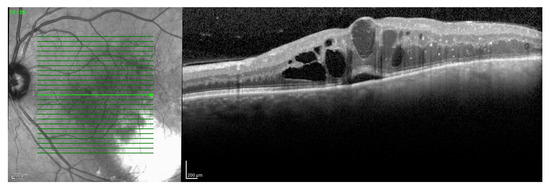

3.2. Radiation Maculopathy